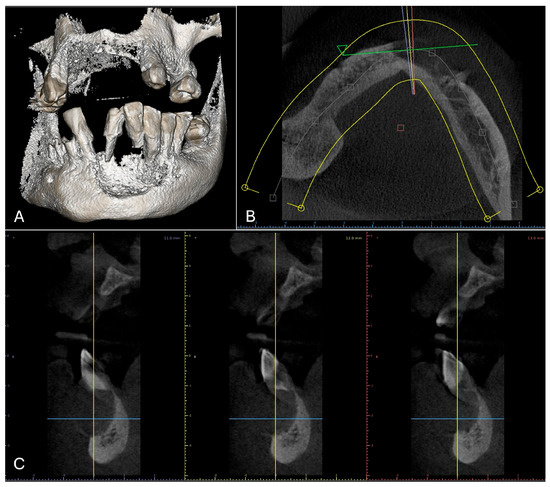

2.1. Examination

2.2. Treatment Procedures and Histopathological Results